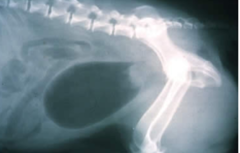

Ischaemia

Intestinal Torsion